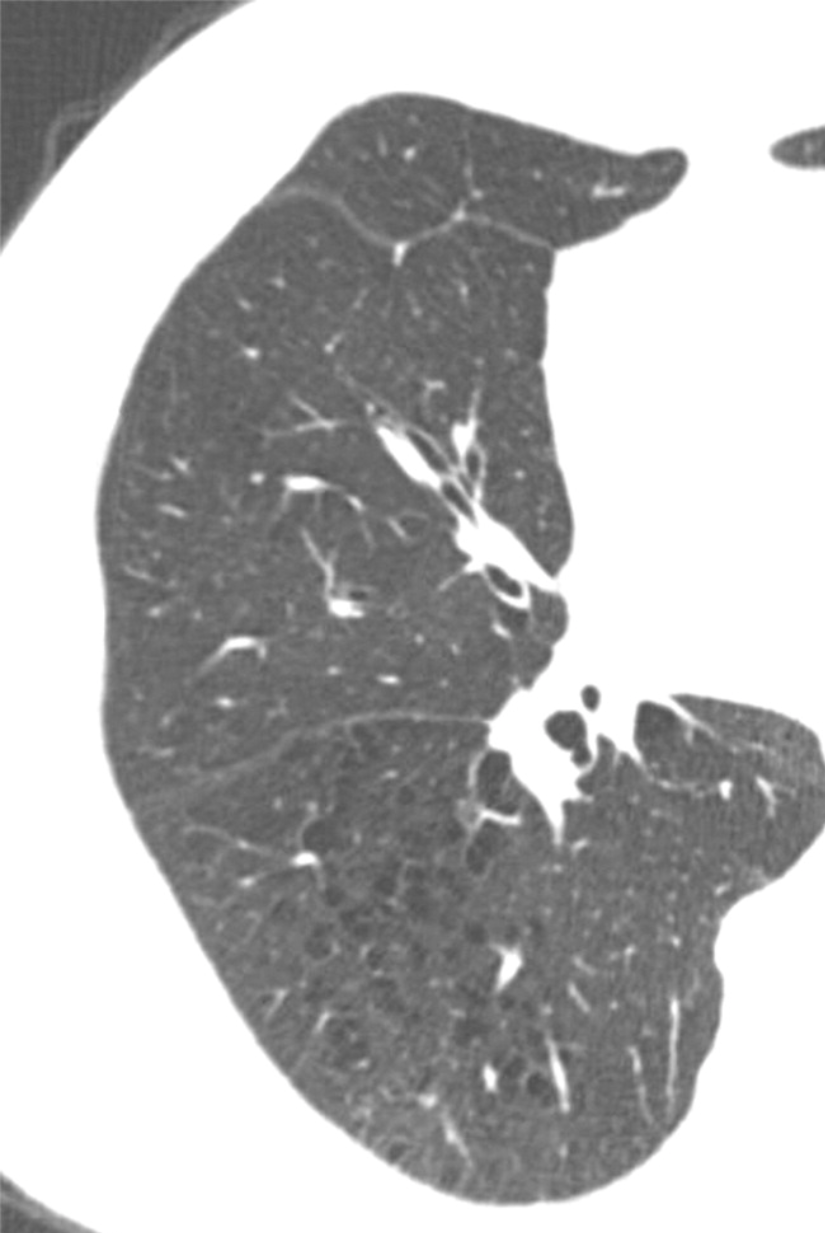

Spectral CT provides greater detail about the extent of ground-glass opacities than conventional CT scans.

Pulmonary artery thrombosis presents differently from acute pulmonary embolism on CT scans.